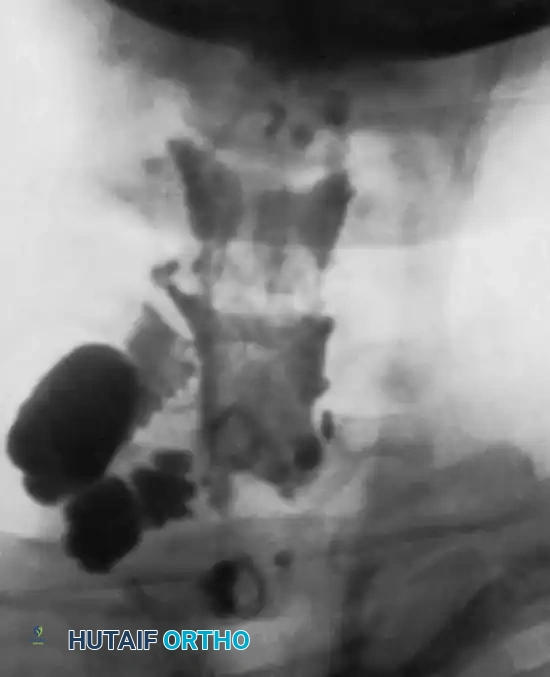

Historically, Pantopaque myelography was utilized to visualize pseudomeningoceles—extravasations of cerebrospinal fluid indicating root avulsion. Rorabeck and Harris noted that 31 of 34 patients with pseudomeningoceles showed no spontaneous recovery. Today, high-resolution MRI is the gold standard, offering superior visualization of the roots, trunks, and cords, as well as surrounding soft tissue edema and neuromas. CT myelography remains highly accurate (75% correlation with intraoperative findings) but should be delayed 6 to 12 weeks post-injury to prevent clotted blood from obscuring pseudomeningoceles.

Fig. 59-18: Myelogram demonstrating a massive pseudomeningocele produced by avulsion of the C7 and C8 roots.